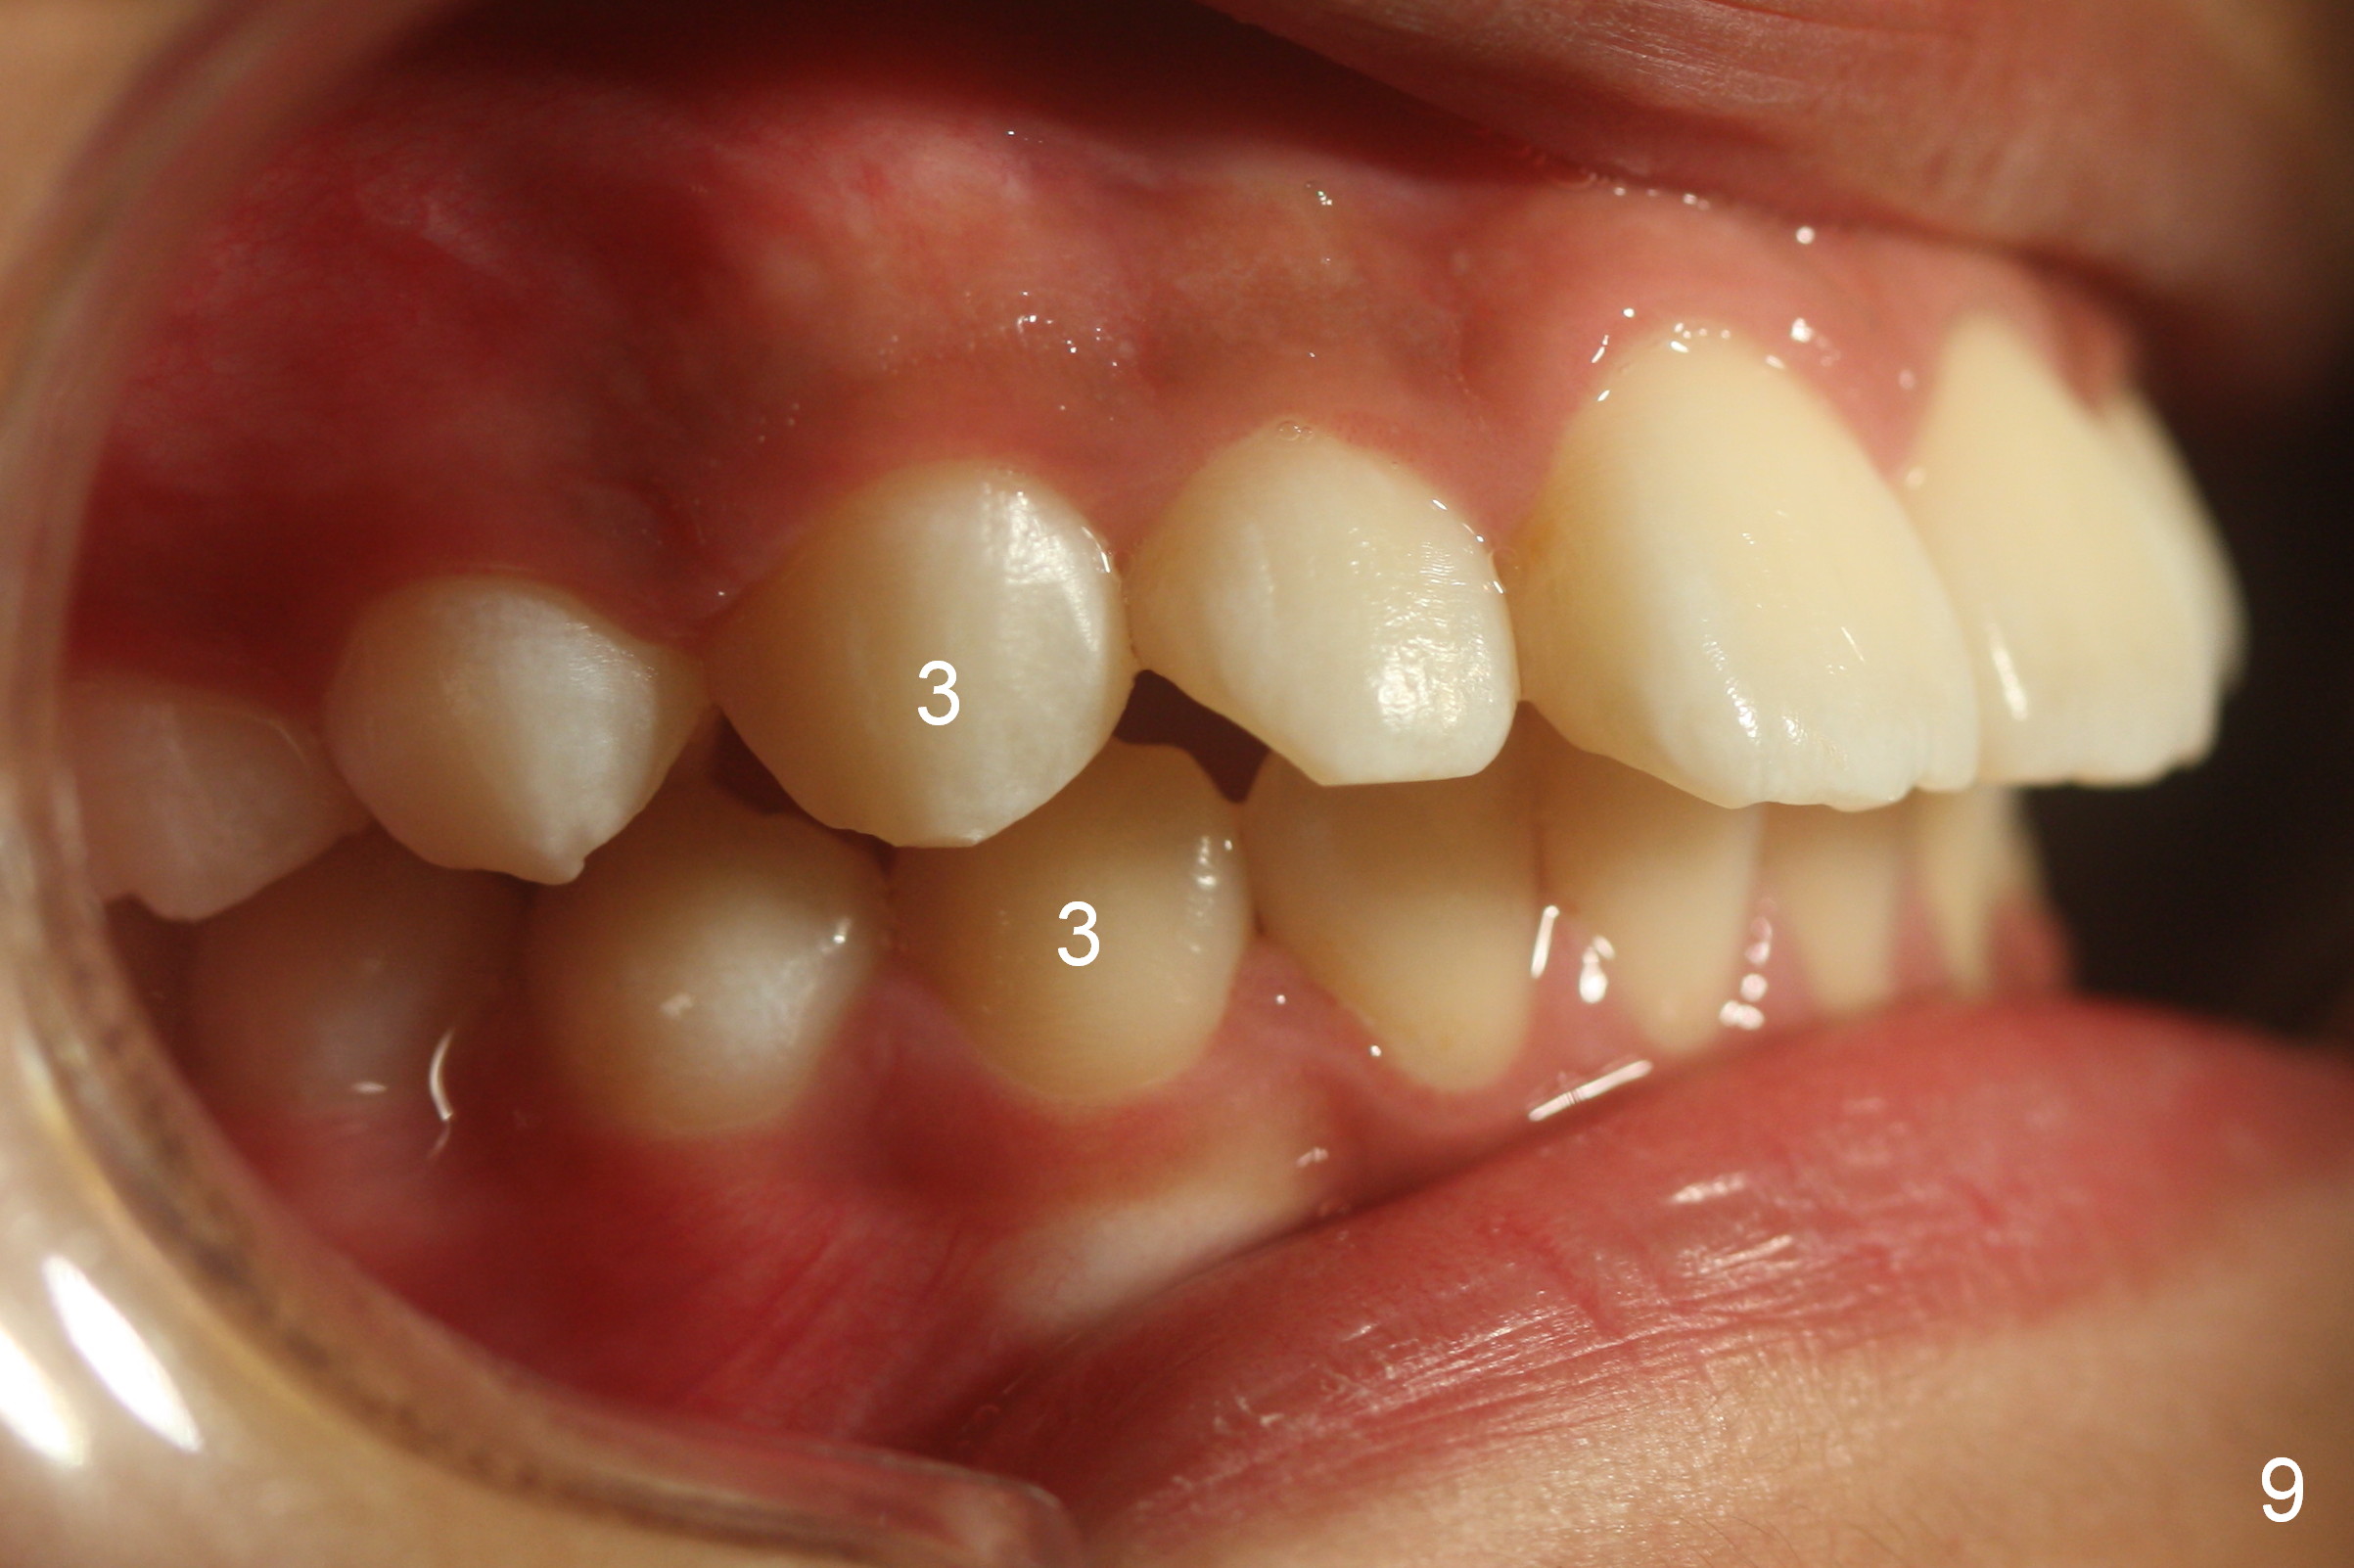

A 11-year-old boy has history of asthma. His father has sleep apnea with similar Class II malocclusion. Pan was taken for the boy 3 years ago (Fig.1). His mother wants to have orthodontic treatment as early as possible, because of protrusive upper anterior teeth. The dentition is permanent except the upper left canine and 1st molar (Fig.7,10,12,13 C, D). It appears that there is bilateral Class II occlusion at canine by half a tooth (Fig.9-12). The malocclusion and facial profile can be easily corrected with extraction of the upper 1st bicuspids.